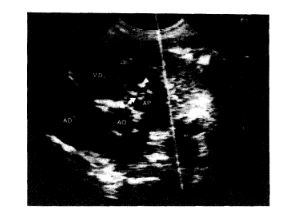

Los recién nacidos con estenosis valvular pulmonar critica necesitan tratamiento urgente . La valvotomía quirúrgica con anastomosis sistémico-pulmonar o sin ella ha sido la terapéutica tradicional . La valvuloplastía pulmonar con catéter balón ha reemplazado a la cirugía en niños; sin embargo, la experiencia en recién nacidos es escasa. Hemos intentado valvuloplastía pulmonar en 14 neonatos con estenosis valvular pulmonar crítica . S61o en 11 el método pudo completarse, mientras que los 3 restantes, que tenían hipoplasia del ventrículo derecho, debieron ser enviados a cirugia . La presi6n sist6lica del ventriculo derecho cay6 de 82 ± 10 a 40 ± 6 mmHg (p < 0,05), el gradiente transvalvular pulmonar disminuy6 de 73 ± 14 a 18 ± 4 mmHg (p < 0,01), mientras que la saturación sistémica de oxígeno se incrementó de 50 ± 4,7 a 83 ± 4 ^i. (p < 0,001) . Un paciente falleció 2 horas después del procedimiento, 3 neonatos fueron enviados a cirugía por mala evolución, mientras que los 7 restantes fueron seguidos entre 1 y 30 meses (X = 10,3) . Todos presentaban gradientes menores a 25 mmHg por ecocardiogafía Doppler . Concluimos que la valvuloplastía pulmonar constituye el método de primera elección en recién nacidos con estenosis valvular pulmonar crítica . Aquellos pacientes con hipoplasia del ventrículo derecho asociada responden pobremente al método y son los que presentan mayor índice de complicaciones.